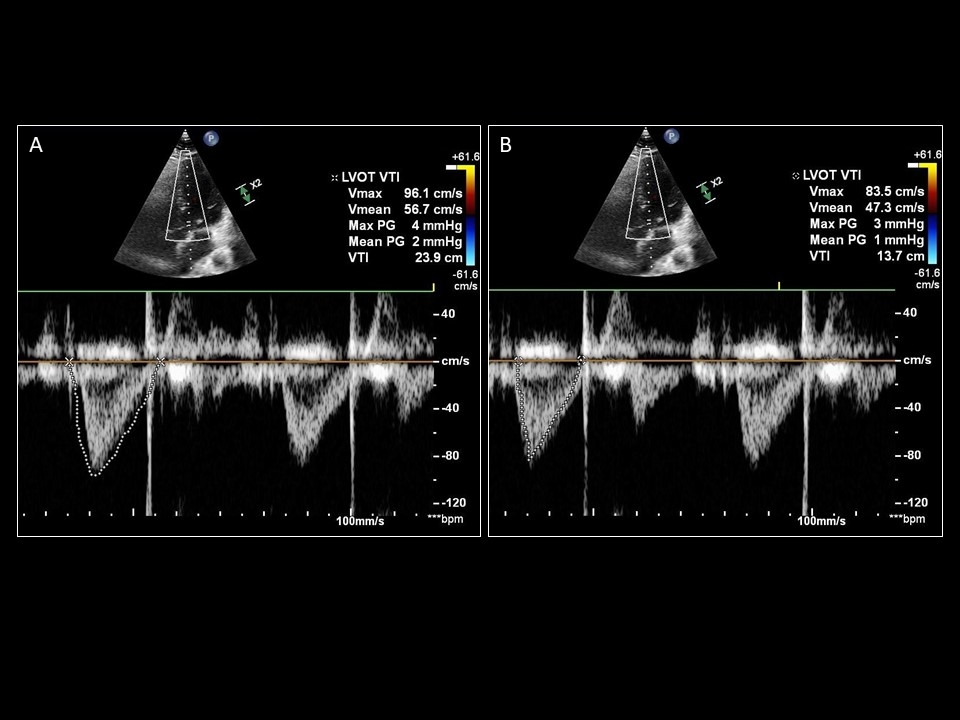

Demonstration of the significant difference in values obtained from over-tracing (A; 23.9cm) and under-tracing (B; 13.7cm) the same LVOT VTI.

Sattin, Burhani, Jaidka, Arntfield. How I Do It: Echocardiographic-based Stroke Volume and Cardiac Output Determination. CHEST.